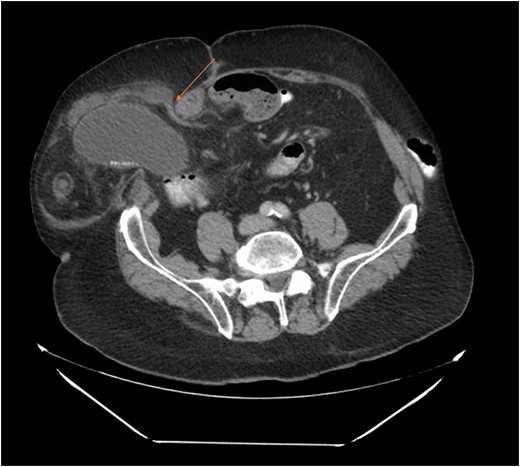

Our patient is an 89-year-old male with a history of a Hartmann’s procedure (2006) for Crohn’s disease of the sigmoid colon followed by a reversal of the colostomy with a diverting loop ileostomy (2008). Due to his comorbidities and age, the patient declined further surgery to reverse his loop ileostomy. Most recently, the patient presented to the emergency room with no ostomy output for the past 14 h, nausea and frequent burping. He reported a burning sensation around his ostomy. His physical examination revealed a large parastomal hernia in the right hemiabdomen and associated tenderness in the right upper quadrant, with no overlying skin changes. His white blood cell count was 8.1 (82.4% neutrophils), and he had normal liver function tests. A computed tomography (CT) scan of the abdomen and pelvis revealed a large parastomal hernia with a wide neck containing a distended gallbladder concerning for acute cholecystitis, as well as a small bowel obstruction with a transition point at the level of the hernia (Figs 1 and 2). A previous CT scan showed the same hernia with a nondistended gallbladder and non-obstructed bowel entering and exiting the stoma (Fig. 3).

Acute cholecystitis causing a small bowel obstruction within a parastomal hernia. Arrow points to transition point.